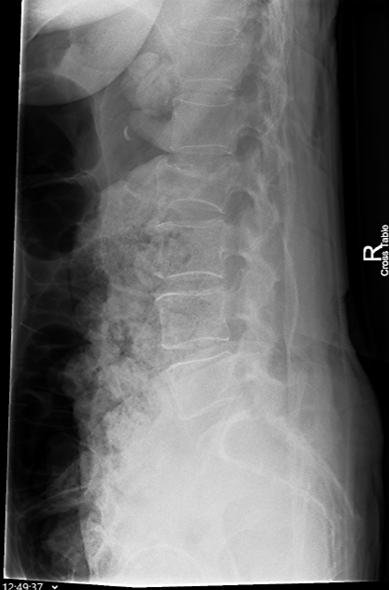

Morfometria radiologica (MRX)

Questa tecnica si avvale di radiografie standard del rachide toracico e lombare eseguite in proiezione laterale. La MRX è storicamente considerata il “gold standard” per la sua eccellente risoluzione spaziale, che permette non solo la misurazione geometrica ma anche una valutazione qualitativa delle limitanti somatiche e degli spazi intervertebrali.5

Tuttavia, la MRX presenta limiti tecnici non trascurabili. La divergenza del fascio radiogeno può causare distorsioni geometriche e il fenomeno della parallasse, rendendo difficile la precisa individuazione dei bordi vertebrali, specialmente in presenza di scoliosi. Inoltre, richiede che il paziente sia posizionato con estrema cura per garantire che i corpi vertebrali siano perfettamente paralleli al piano sensibile, onde evitare la proiezione di “doppi contorni” delle limitanti somatiche che invaliderebbero la misurazione.